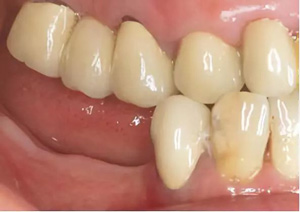

圖2-圖6:2013 年10 月15 日口內(nèi)狀況。

口外檢查未發(fā)現(xiàn)異常。牙齒和牙周狀態(tài)如圖1 和2-6所示??傮w來(lái)說(shuō),已有的修復(fù)體已不完善。第一次就診時(shí),檢查發(fā)現(xiàn)17、15、11、36、45 和46 號(hào)牙齒已缺失。16、14、12、27、37 和35 號(hào)牙齒已做過(guò)根管治療。所有剩余的牙齒牙髓活力測(cè)試均正常,叩診檢查未見(jiàn)異常。橋基牙37 已發(fā)生大面積的繼發(fā)齲,33 號(hào)牙齒齲壞和43 號(hào)牙齒繼發(fā)齲。16 和14 號(hào)牙齒根管充填不足且有根尖周炎。35 號(hào)牙齒的根管充填似乎是邊緣封閉、無(wú)氣泡,但也欠充。所有需要保留的牙齒的平均牙周附著喪失為5-6mm(最大9mm),探診深度(ST)為4-5mm(最大8mm)。27 號(hào)牙齒單獨(dú)的探診深度已達(dá)15mm。牙齦緣普遍松軟,下頜前牙舌側(cè)區(qū)域附著堅(jiān)硬的菌斑。整個(gè)邊緣牙齦發(fā)生炎癥性改變,特別是腭側(cè)區(qū)域。